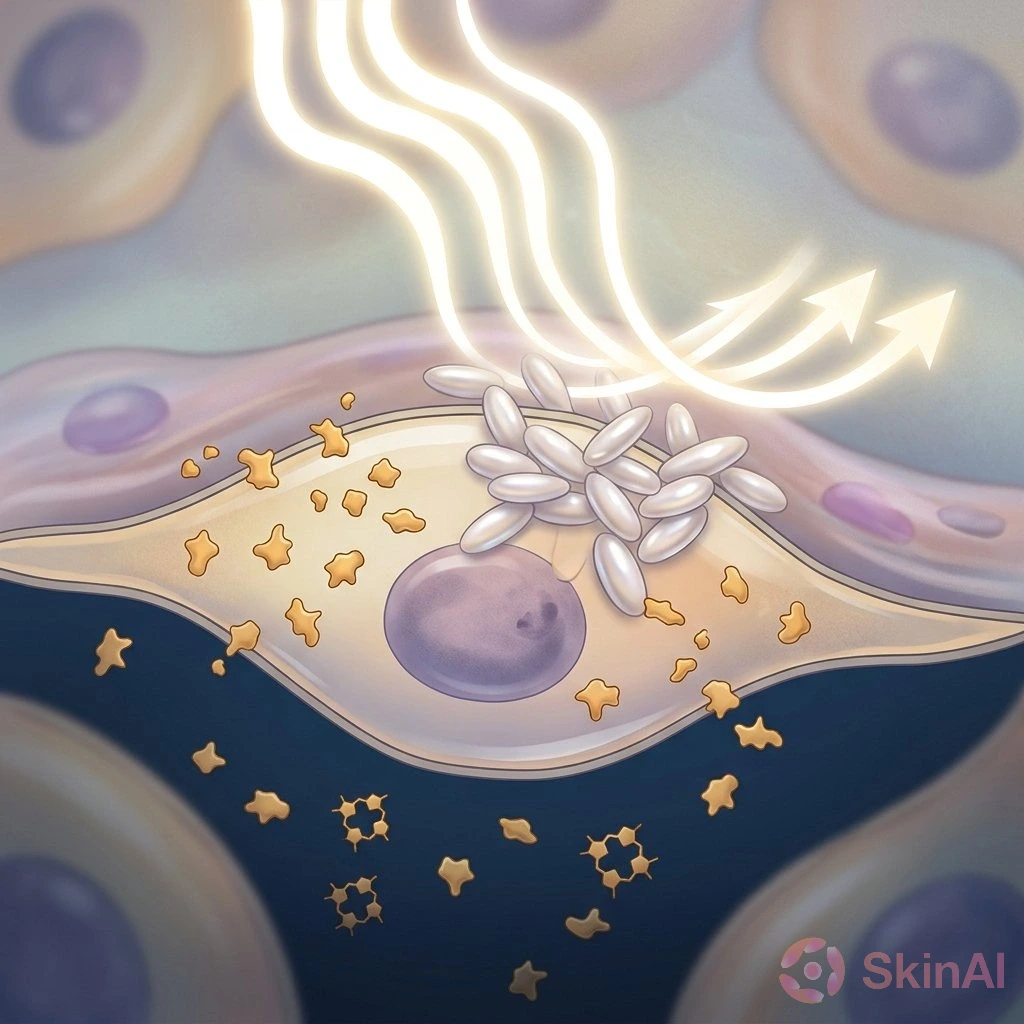

Malassezia Folliculitis vs Acne: How to Spot and Treat the Difference

Discover how to tell Malassezia folliculitis from acne and learn the best treatments for each to clear your skin effectively...